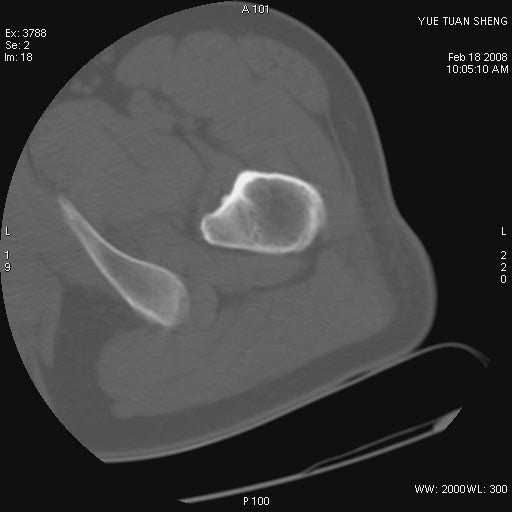

患者,男,56岁,左髋部疼痛1个月,x线:左股骨头高密度影,性质待定,右侧正常。左髋ct如图

左股骨颈区椭圆形磨玻璃样影,边缘明显硬化环环绕,其内见斑点状类钙化高密度影考虑 良性骨病-----骨纤,骨化性纤维瘤,内生软骨瘤。